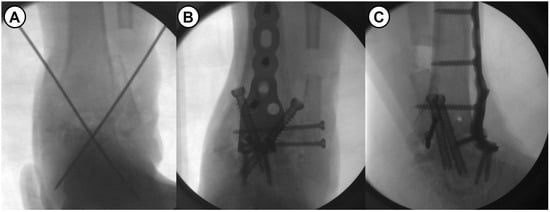

Figure 5.

(A) Intraoperative fluoroscopic image shows a proximally reposition of the talus and temporary k-wires fixation. (B,C) With the ankle in neutral position, the rigid fixation with anterior fusion plate and transarticular screws.

All surgeries were performed by a single senior surgeon with over 15 years of experience. Shortening ankle arthrodesis basically consisted of fibular osteotomy, internal fixation with anterior fusion plate, and autogenous bone grafting. A 10 cm sized anterior midline longitudinal skin incision was made and careful soft tissue dissection between the tibialis anterior and extensor hallucis longus tendons was performed to approach into the ankle joint. Following excision of the joint capsule, the remaining cartilage and osteophytes were removed, and sufficient subchondral preparation with multiple drilling to stimulate bone-marrow bleeding was performed (Figure 3). In cases of failed TAA, all prosthesis and metallosis debri were meticulously removed. To maximize the contact area and to minimize the large defect space between tibial plafond and talar dome, fibular osteotomy with protection of the anterolateral neurovascular bundle was performed approximately 1–5 cm above the upper margin of the distal tibiofibular syndesmosis (see Figure 4). Following a transverse osteotomy, the proximal and distal parts were completely displaced, and a segmental bone fragment of about 1–3 cm was harvested from the proximal part if necessary for bone grafting. Then, the distal tibiofibular syndesmosis was dissociated by dissecting the interosseous ligament and anterior and posterior tibiofibular ligaments. The talus was proximally repositioned with maximal compression force. Any remaining defect was filled with an autograft cancellous bone (an average of 11.8 cc) harvested from the proximal tibial metaphysis. With the ankle placed in neutral position, two partially threaded cannulated screws (6.5 mm in diameter) were inserted in a cross-articular manner. Finally, the Titanium Ankle Fusion Plating System (Arthrex, Naples, FL, USA) was secured with locking compression screws (Figure 5). Under C-arm guidance, the final alignment of the ankle and implant position were checked.